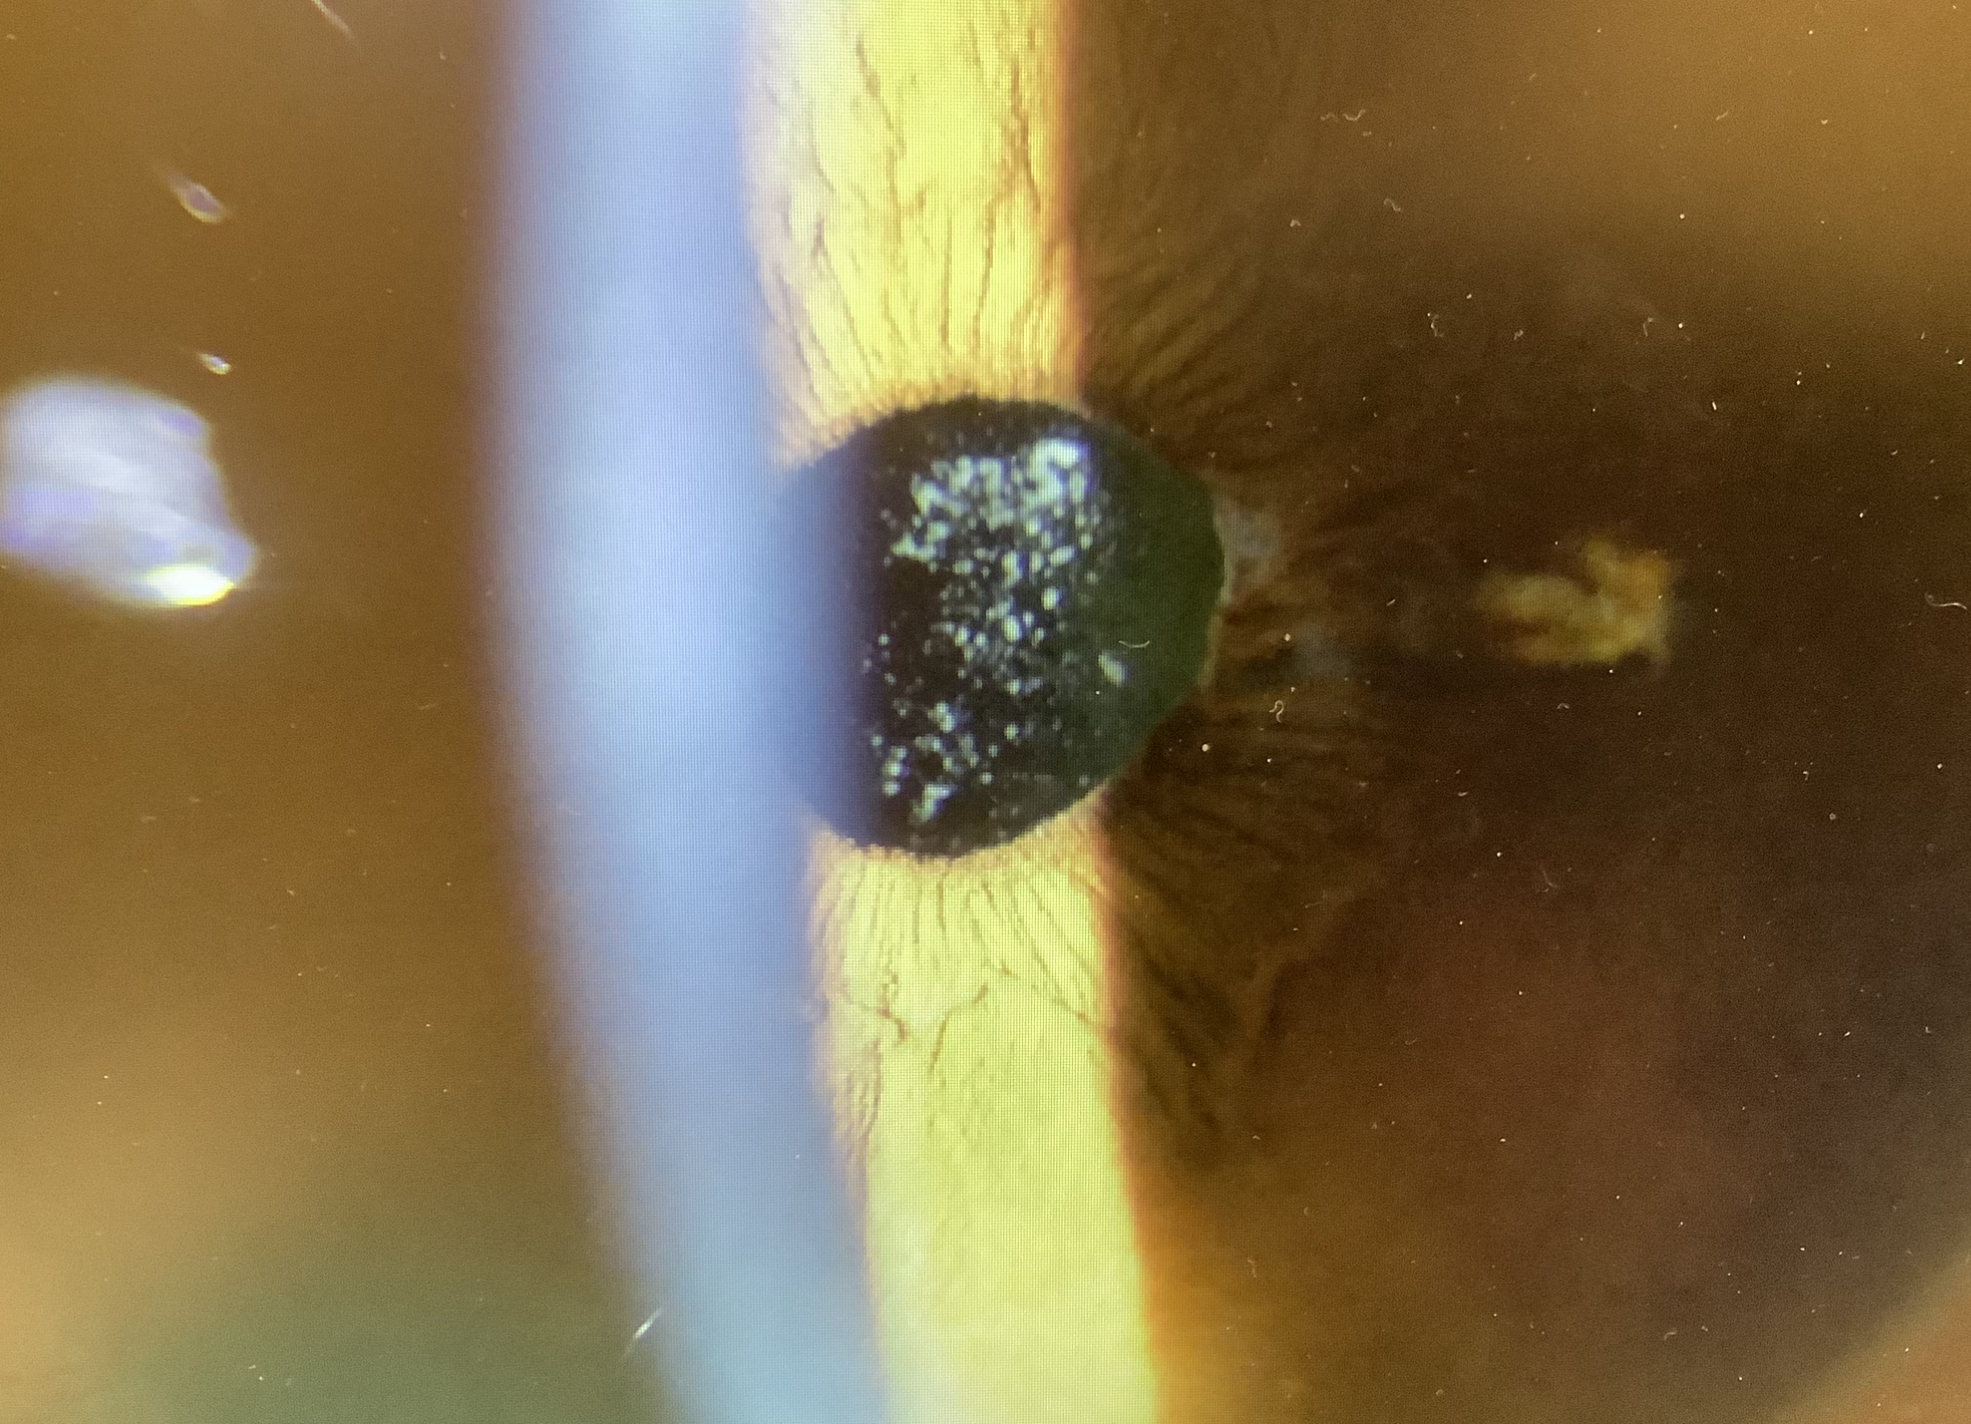

アドオンレンズ挿入後の方は先週の金曜日にレンズを入れて翌日は問題なかったのですが、その次の日くらいから『ちょっとかすむ』と月曜日にいらっしゃり、感染症とかレンズに対する拒絶反応の炎症ではなさそうでしたが、角膜の裏面とレンズの表面に濁りが付着していて、それが症状の原因と思われたので、今日、洗浄させていただきました。もしかすると、術後の一過性の反応で、経過で自然軽快の可能性もあるかと思いましたが、濁りが取れなくなってしまうと嫌だなと思ったので、洗わせていただきました。患者さまには処置を受ける負担にはなってしまって申し訳なかったですが、治療は待ってもよい時と早めが望ましい時(急がないといけない時)とあり、今回は早めがよいと思ったので、ご理解いただきどうもありがとうございました。

↑アドオンレンズ表面についた濁り。